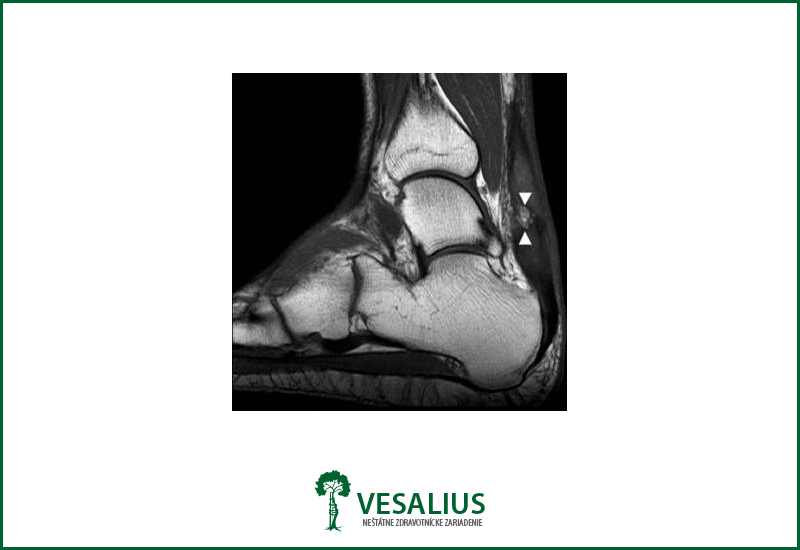

Diagnóza sa stanoví jednak vyšetrením, kedy v akútnom štádiu lekár hmatá jednoznačný defekt v oblasti ruptúry a tiež je oslabená sila pri pohybe v členku. Pri čiastočných ruptúrach je nápomocné vyšetrenie magnetickou rezonanciou resp. ulptrazvukom.